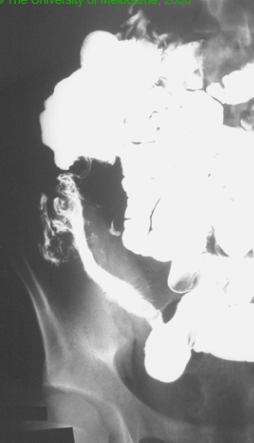

66yo patient presents with dysphagia to solids and liquids. This is aided by postural change. Associated history of mild, ongoing weight loss and regurgitation

Achalasia